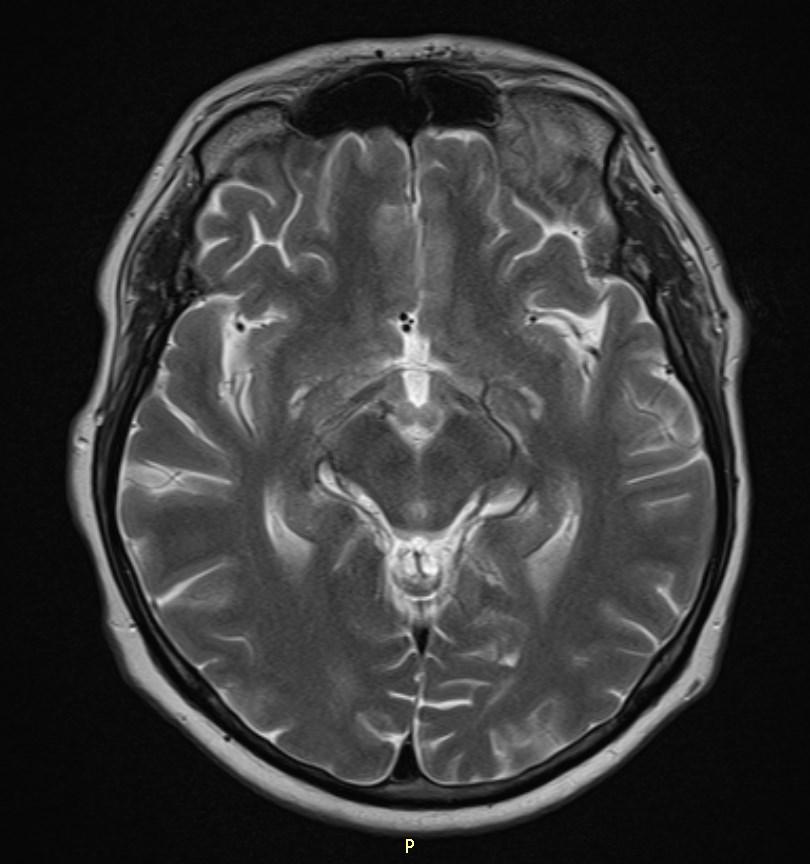

MRI images revealed hyperintensities in the periaqueductal region and the medial thalami.

T2/FLAIR: symmetrically increased signal intensity in the mamillary bodies, dorsomedial thalami, tectal plate, periaqueductal area, and around the third ventricle.